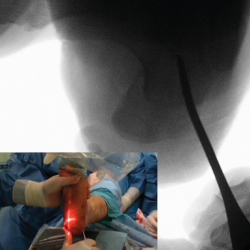

Figura 4. Imagen fluoroscópica de la fresa suelta introducida y su correspondencia en cirugía.

Ayudándose del mosquito para separar las partes blandas, se introduce una fresa Shannon 2 o 3 × 20 mm (FH Orthopedics, Mulhouse, Francia) en el vértice de la V. Comprobada la correcta posición de la fresa en la fluoroscopia (desconectando el motor de la fresa) (Figura 4), esta se avanza perpendicularmente al eje del calcáneo hasta atravesar la segunda cortical. Inclinando la fresa se pueden obtener diferentes desplazamientos, si bien, para conseguir un mayor desplazamiento, se recomienda avanzar perpendicularmente al eje. Si se quiere conseguir cierto efecto de descenso además de medialización de la tuberosidad se dirigiría la fresa en dirección de dorsolateral a plantomedial unos 15-30° respecto a la perpendicular del eje del calcáneo. Si lo que se quiere es obtener un efecto de elevación (beneficioso en el cavo posterior), la dirección sería la contraria, es decir, de lateroplantar a dorsomedial. Se podría obtener también acortamiento del calcáneo si la fresa se dirige de lateral distal a medial proximal, e incluso un alargamiento (de lateral proximal a medial distal), aunque esto último dificultaría el desplazamiento por la tensión de los tejidos(13).

Figura 5. Imagen fluoroscópica del trazo dorsal de la osteotomía y su correspondencia en cirugía.

La fresa se coloca en línea con el trazo de osteotomía dibujado en la piel, primero el dorsal y después el plantar (Figuras 5 y 6), y va cortando la pared lateral y el hueso esponjoso del calcáneo y progresando paulatinamente hasta alcanzar la segunda cortical y cortarla cuidadosamente. Se recomienda no superar en 6.000 rpm la velocidad de la fresa para evitar la osteonecrosis térmica. A pesar de que el procedimiento se realiza sin isquemia para que la sangre refrigere el calor de la fresa, se recomienda que el ayudante aporte suero salino para contribuir a tal efecto.

Figura 6. Imagen fluoroscópica del trazo plantar de la osteotomía y su correspondencia en cirugía.